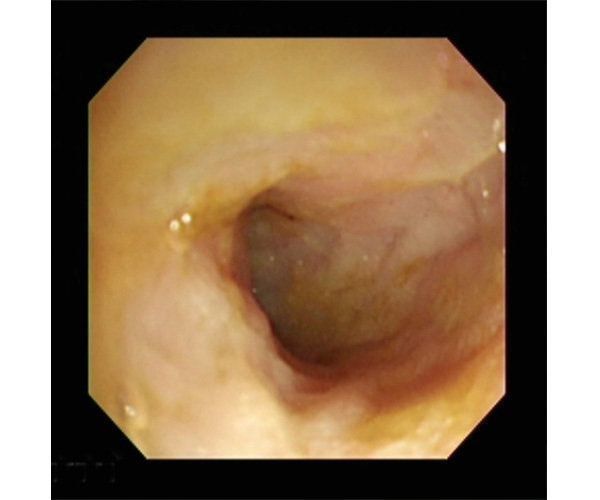

「たまに吐く」「おなかがゆるい」といった慢性的な嘔吐(おうと)や下痢がみられる病気です。内視鏡で腸の組織の一部を切り取って検査をすることで病気を診断できます。

内視鏡で見た炎症性腸疾患を起こしている犬の腸内。粘膜がでこぼこしている。